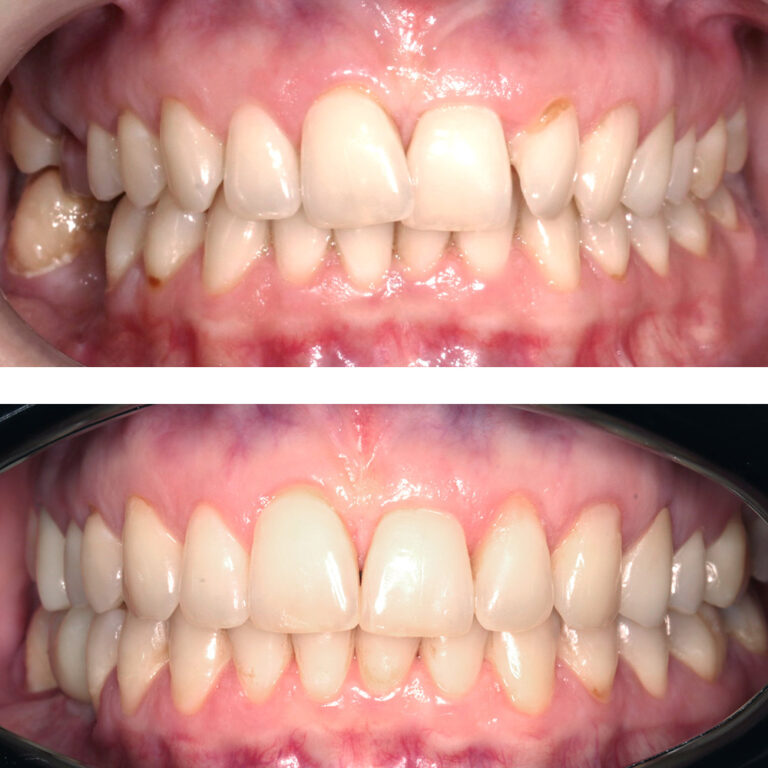

Кейс 21

Юрченко Павел Николаевич

Количество кап ВЧ 32

Количество кап НЧ 32

ДО

ПОСЛЕ